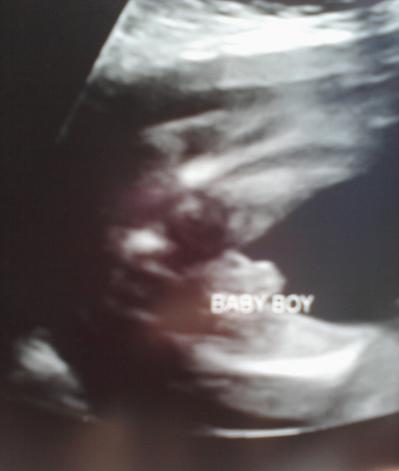

So happy to be posting here! Here are my pics from 13 weeks and 20 weeks...

Oh Roonarpia I am THRILLED for you!!!! Congratulations :-) Are your girls so excited to have a little brother?!?! Wonderful news!